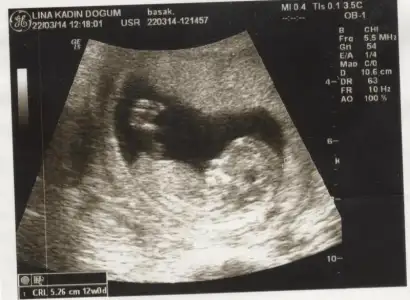

selam kızlar daha once burada usg goruntulerını paylasmıstım :) net sonucu yazayım dedım,erkek..

ya kızlar benim iki hafata önceki ultrasonum var belli midir? dr erkek muhtemelen dedi ama kesin demedi. yeni ultrasonu ekleyemedim bir türlü ışık patlaması oluyor. çocuğun kafası kocaman görüyodu korktum ya siiznkilerde de öyle oldu mu? kötü bişey olsa dr söylerdi dimi? ya da ultrasn eski diye mi öyle çıktı?